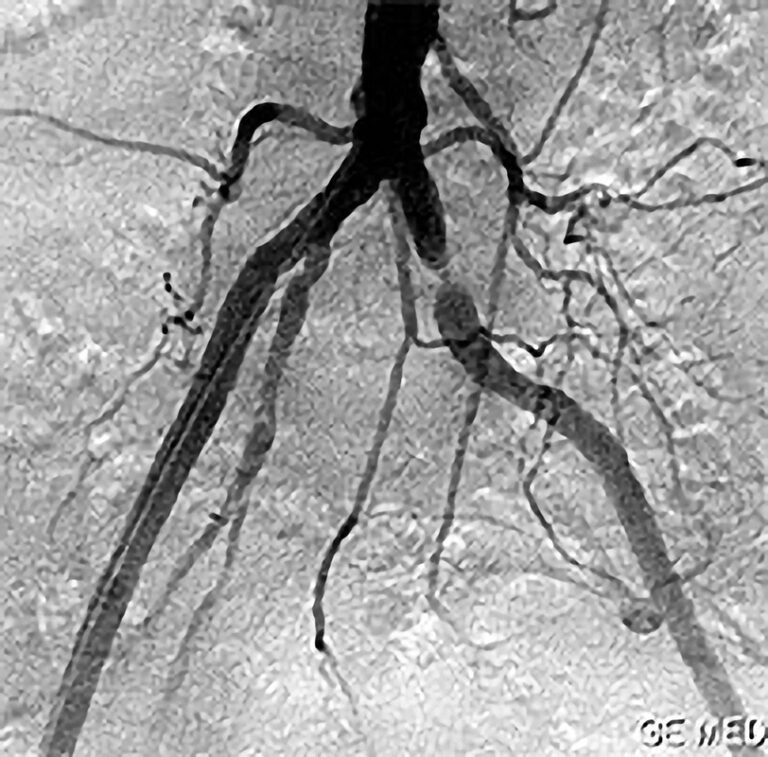

Die PTA (Perkutane Transluminale Angioplastie) im Beckenbereich ist ein minimalinvasives Verfahren zur Behandlung von verengten Beckenarterien. Dabei wird ein dünner Katheter mit einem Ballon über die Leiste in die verengte Arterie eingeführt. Der Ballon wird an der Engstelle entfaltet und dehnt die Arterie auf, um den Blutfluss zu verbessern. Oft wird zusätzlich ein Stent eingesetzt, um die Arterie dauerhaft offen zu halten. Die PTA wird meist in örtlicher Betäubung durchgeführt und ermöglicht eine schnelle Erholung. Sie ist eine bewährte Alternative zur offenen Operation bei Durchblutungsstörungen im Becken- und Beinbereich.